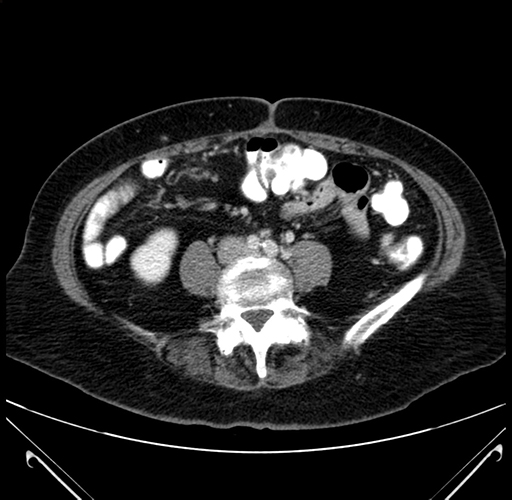

Axial Venous

Coronal Venous